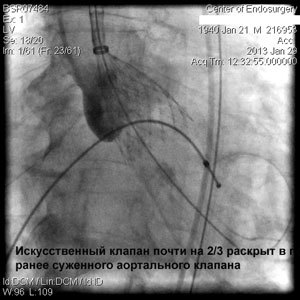

Через прокол (или маленький разрез) в артерии, в сжатом состоянии проводят искусственный клапан, который расширяется при его установке на месте поврежденного аортального клапана. После раскрытия клапан начинает функционировать и восстанавливает полноценную и нормальную работу аорты.

Впервые в России частная многопрофильная клиника «Центр эндохирургии и литотрипсии», опираясь только на собственные ресурсы и не расходуя бюджетные средства на здравоохранение, выполнила эту уникальную и высокотехнологическую операцию у двух пациентов в возрасте 74 и 82 года.